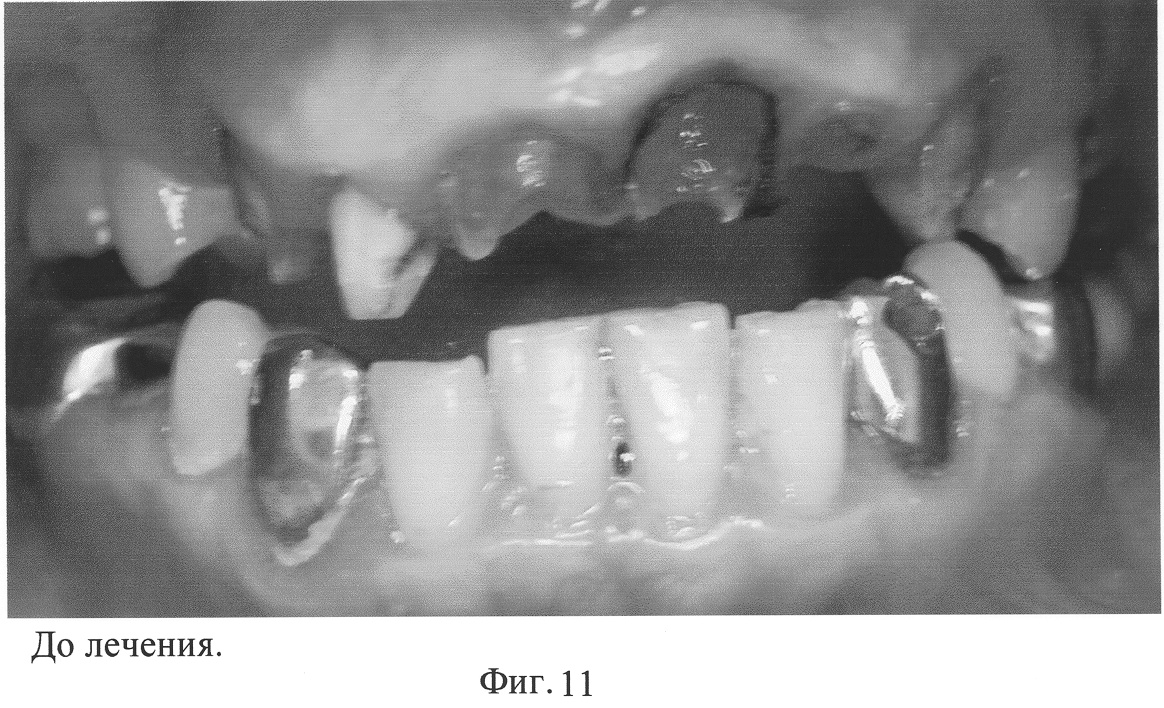

Пациент Т., 28 лет.

Жалобы: на эстетическую неудовлетворенность, на полное отсутствие коронковой части 11.

Анамнез: Со слов больного, 11 зуб ранее неоднократно лечен по поводу осложненного кариеса. Около полугода тому назад была проведена реставрация 11 с помощью композитных материалов. Три дня тому назад произошел отлом коронковой части 11.

Объективно: Состояние удовлетворительное, внешний осмотр без особенности. Слизистая оболочка полости рта бледно-розового цвета. Прикус ортогнатический. Отсутствует коронковая часть 11. Перкуссия зуба безболезненна. На прицельной рентгенограмме в периапикальных тканях изменения нет, канал корня запломбирован полностью.

Рекомендовано реставрировать отсутствующую коронковую часть 11 с применением сборного армирующего штифта.